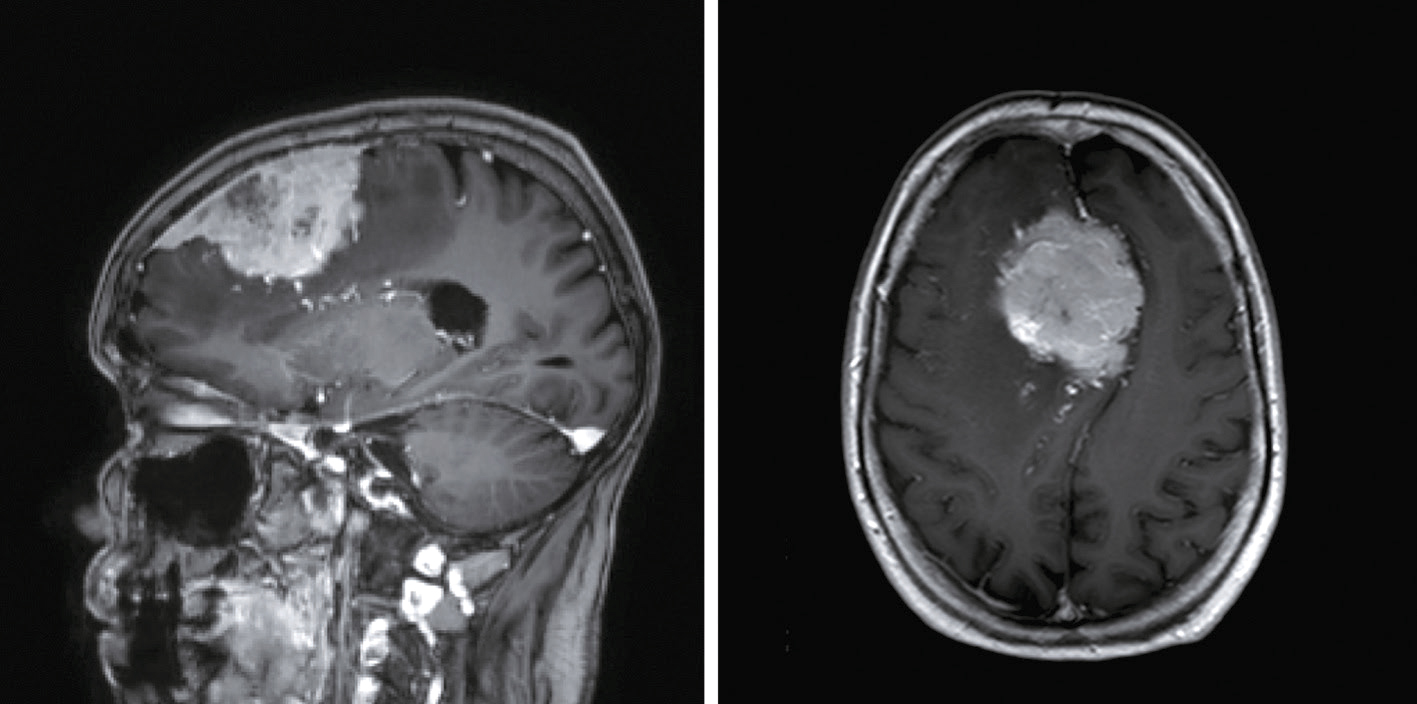

Devant cette atteinte du nerf III avec douleurs associées, vous souhaitez éliminer la présence d’un anévrisme carotidien, raison pour laquelle vous décidez de réaliser une IRM cérébrale avec ARM cervicale. Il n’y a pas d’anévrisme mais d’autres images attirent votre attention. Quelles sont les coupes et séquences utilisées pour ces deux images (fig. 31.12 et 31.13) ?

L'image montre une coupe transversale d'un cerveau humain obtenue par imagerie par résonance magnétique (IRM). Cette image est en niveaux de gris et présente des structures cérébrales distinctes. On peut observer les hémisphères cérébraux, séparés par la fissure interhémisphérique. Les zones plus claires sur l'image représentent des anomalies ou des lésions, qui peuvent être dues à diverses conditions médicales telles que la sclérose en plaques, les tumeurs, ou les accidents vasculaires cérébraux. Les zones sombres au centre de l'image correspondent aux ventricules cérébraux, qui contiennent le liquide céphalorachidien. Cette image est intéressante car elle permet aux professionnels de la santé de diagnostiquer et de surveiller les maladies neurologiques en visualisant les structures internes du cerveau et en identifiant les anomalies. Les détails observables, comme la localisation et la taille des lésions, sont cruciaux pour une évaluation approfondie. Ce type d'imagerie aide à comprendre l'étendue des dommages et à planifier des traitements appropriés. En analysant ces images, les médecins peuvent mieux comprendre la santé cérébrale et prendre des décisions éclairées concernant les soins à apporter au patient.

L'image montre une coupe transversale d'un cerveau humain obtenue par imagerie par résonance magnétique (IRM). Cette image en niveaux de gris présente les structures internes du cerveau, y compris les circonvolutions et les sillons. Les variations de teintes indiquent différentes densités de tissus et de liquides. Les zones plus claires peuvent correspondre à des anomalies ou des lésions, telles que des tumeurs, des plaques ou des signes de maladies neurologiques. Les zones sombres au centre de l'image représentent les ventricules cérébraux, remplis de liquide céphalorachidien. Cette image est utilisée pour diagnostiquer et surveiller diverses pathologies cérébrales, fournissant des informations cruciales pour les professionnels de la santé. L'IRM est une technique non invasive qui permet de visualiser avec précision les détails anatomiques du cerveau sans utiliser de rayonnement ionisant. Grâce à cette image, les médecins peuvent identifier des anomalies, évaluer leur étendue et planifier les traitements nécessaires pour les patients atteints de troubles neurologiques. Les coupes transversales du cerveau montrent également les principales régions cérébrales, permettant une meilleure compréhension de la structure et des fonctions du cerveau humain.

- A coupes axiales en séquence T2 injectées

- B coupes axiales en séquence T1 non injectées

- C coupes sagittales en séquence T2/FLAIR

- D coupes axiales en séquence T2/FLAIR

- E coupes axiales en séquence 3D TOF

Les lésions multiples visualisées sur cette IRM cérébrale (une ou plusieurs propositions exactes) :

- A concernent les territoires périventriculaires

- B sont en hyposignal T2/FLAIR

- C ne sont pas responsables d’un effet de masse

- D sont localisées dans la substance grise

- E sont localisées dans la substance blanche